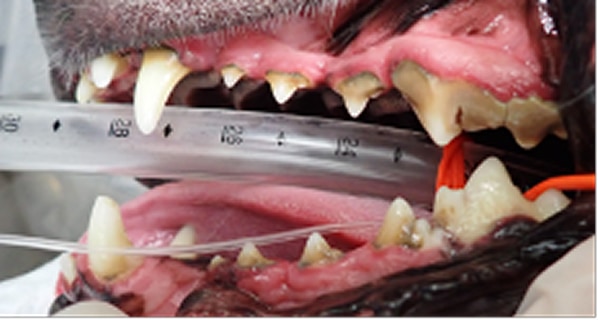

犬の歯周病は、口臭や歯のぐらつきなどから始まり、進行すると歯の痛みや脱落、全身疾患につながるリスクがあります。歯周病はプラークや歯石の蓄積によって引き起こされるもので、これが原因で歯周組織が徐々に破壊されていきます。早期の段階では、炎症や腫れを伴い、犬が口元を気にする仕草が見られることが多いです。しかし、口の痛みがあっても食欲が落ちにくいため、見過ごされやすいので注意が必要です。

治療は内科療法で症状を軽減することはできますが根治は難しく、根本的には全身麻酔下での歯石除去、歯周ポケットのクリーニング、抜歯が必要になることもあります。